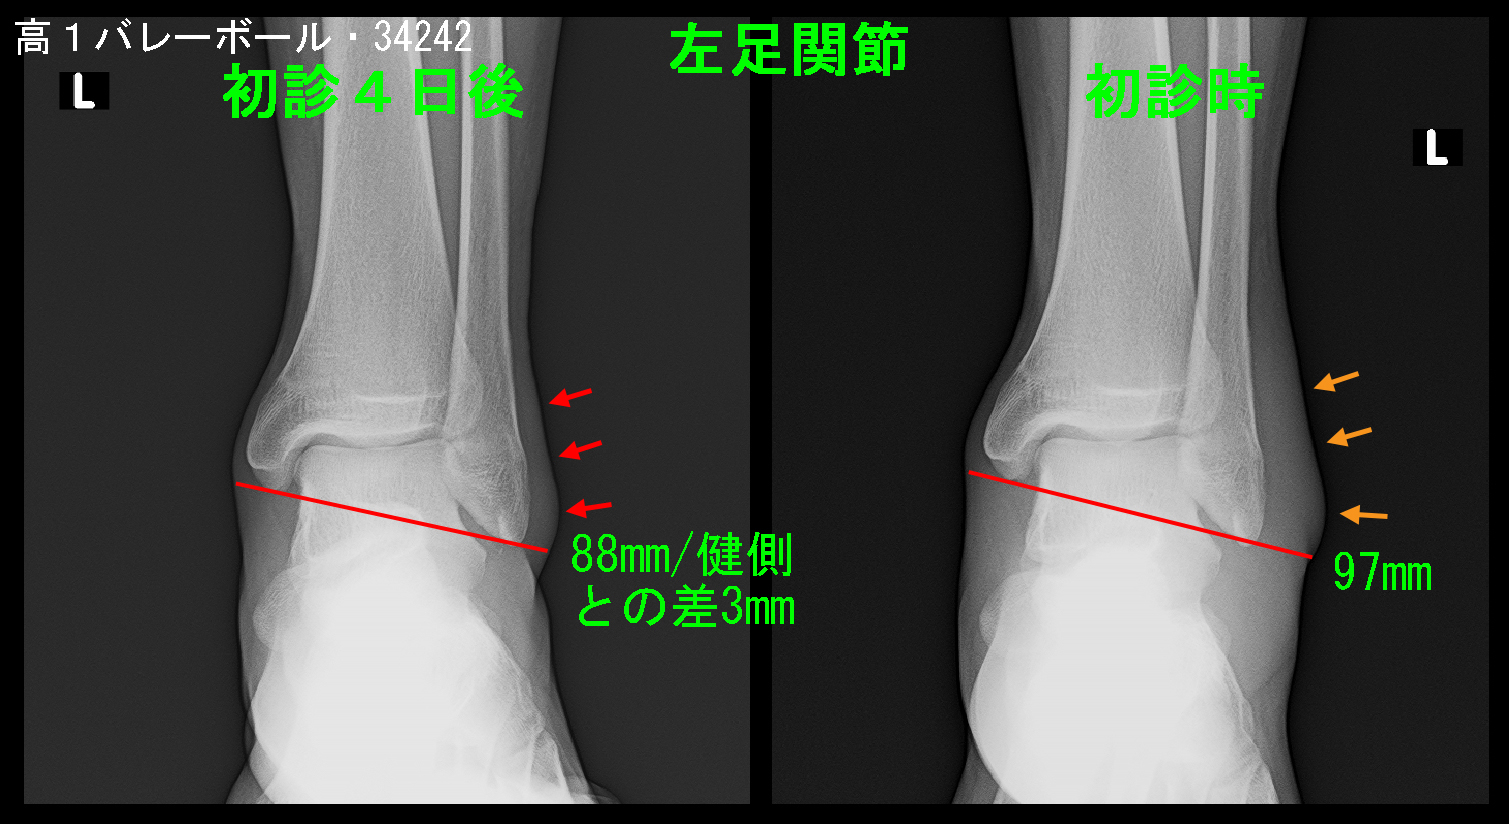

初診の4日後の5月4日にギプスシーネ固定のチェックのために受診してもらうと、患者さんはギプスシーネを外して受診し、「普通に歩けるので練習を始めたい」と言ってきました。

その時のレントゲン像ですが、97mmあった左足関節幅は88mm(健側との差は3mm)に軽減していました。原則私は患者さんの意向に沿った対応を心がけているので、「じゃ、やってみたら」と答えましたが、練習を開始すれば痛みと腫れが再発して、受診してくることになるだろうと思っていましたが、その患者さんは再診されることはありませんでした。治療した私も驚くほどの治療効果でした。